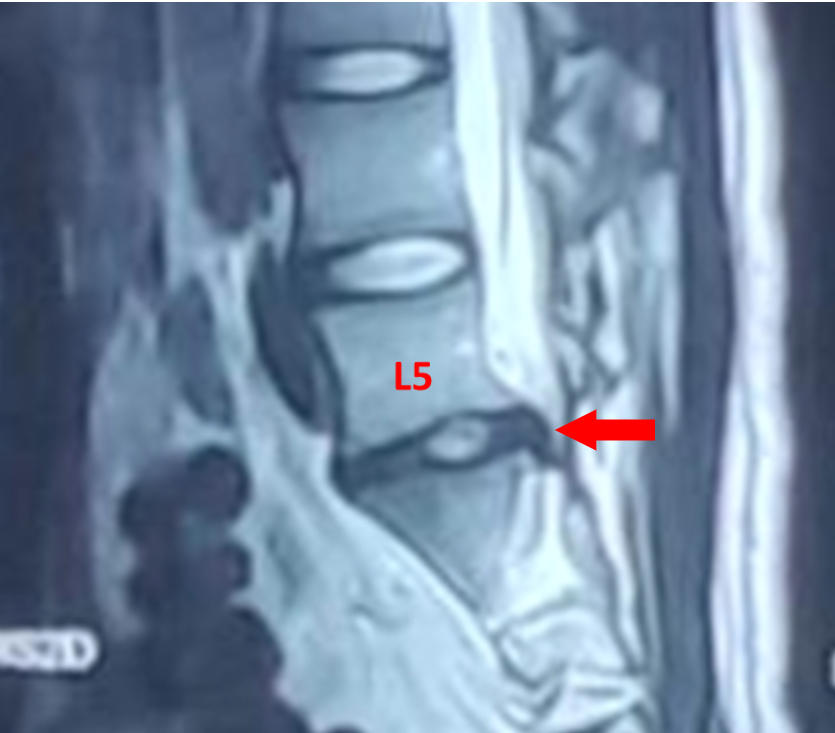

在家人的陪同下,小祁到家附近医院就诊,经腰部椎磁共振检测发现,小祁腰5/骶1椎间盘左后突出。

据了解,急性外伤是腰椎间盘突出的诱发因素,可导致椎间盘发生破裂,髓核、纤维环甚至终板向后突出,严重者压迫神经产生症状。由于长期运动姿势不良,加上3个月前意外受伤,在两者的共同作用下,最终导致小祁腰椎间盘突出。